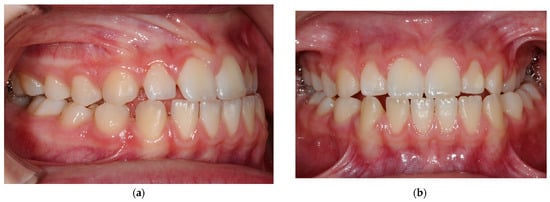

3.4. Treatment Results